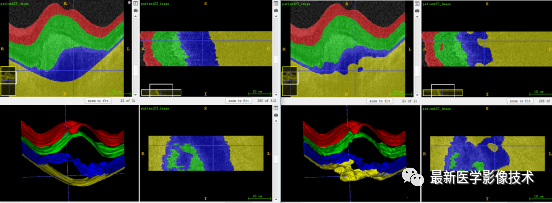

5、验证集分割结果

验证集平均结果

可以看到最大的错误发生在第 3 类(RPE 和 BM 之间的表面),导致错误分割的因素是显著的类别不平衡,如下所示。